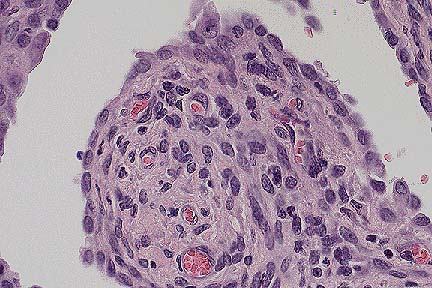

Higher magnification of photograph above showing bile duct hyperplasia, neovascularization, and lymphocytic inflammation. (HE, 400X, 59K)

Contributor's Diagnosis and Comments: Liver: Cholangiohepatitis, lymphoplasmacytic, chronic, periportal, diffuse and bridging, with nodular hyperplasia and marked bile duct proliferation, Domestic Shorthair cat, feline.

Feline cholangitis/cholangiohepatitis syndrome occurs in three histologic forms: suppurative cholangitis/cholangiohepatitis, long-term nonsuppurative cholangitis/cholangiohepatitis, and biliary cirrhosis. The three forms are thought to be progressive stages of the same disease. Initial inflammation of the biliary system spreads to the adjacent hepatic parenchyma. The long-term result is portal fibrosis and biliary hyperplasia. The etiology of the disease is unknown, although immune-mediated mechanisms have been proposed. Additionally, bacterial and parasitic infections (including toxoplasmosis) have been associated with suppurative cholangitis. Many cats with the disease respond favorably to corticosteroid and/or antibiotic therapy. Biochemical findings vary. Aspartate aminotransferase, alanine aminotransferase, and alkaline phosphatase enzymes are often high in the suppurative form, but can become normal as the disease progresses. Hyperbilirubinemia is common. In the present case, a causal relationship was not established between the toxoplasmosis and liver lesions.

Nonsuppurative cholangiohepatitis is characterized by portal infiltrates of plasma cells and lymphocytes, bile duct hyperplasia, and periportal fibrosis; small numbers of neutrophils may be present. Nonsuppurative cholangiohepatitis has also been associated with pancreatitis. Cats less than 4 years of age are primarily affected.

Biliary cirrhosis is presumed to result from progressive cholangiohepatitis; however, the etiology is unknown. Histologically, there is prominent bridging portal fibrosis, bile duct hyperplasia, nodular hyperplasia, and chronic inflammation of varying severity. Regardless of etiology, the prognosis for any form of cholangiohepatitis is guarded due to a generally poor response to therapy.

Some attending the conference diagnosed cholangiocarcinoma; however, there are several features that argue against a neoplastic process. At the center of most of the areas of bile duct hyperplasia, there are pre-existent portal structures, suggesting a diffuse proliferative lesion rather than widespread portal invasion of neoplastic cells. Additionally, there is little cellular atypia of the proliferating epithelial cells, the proliferating ducts are linedby a single layer of cells, and the mitotic rate is low. Also, nodular hepatocellular regeneration and biliary hyperplasia are not commonly associated with cholangiocarcinoma.